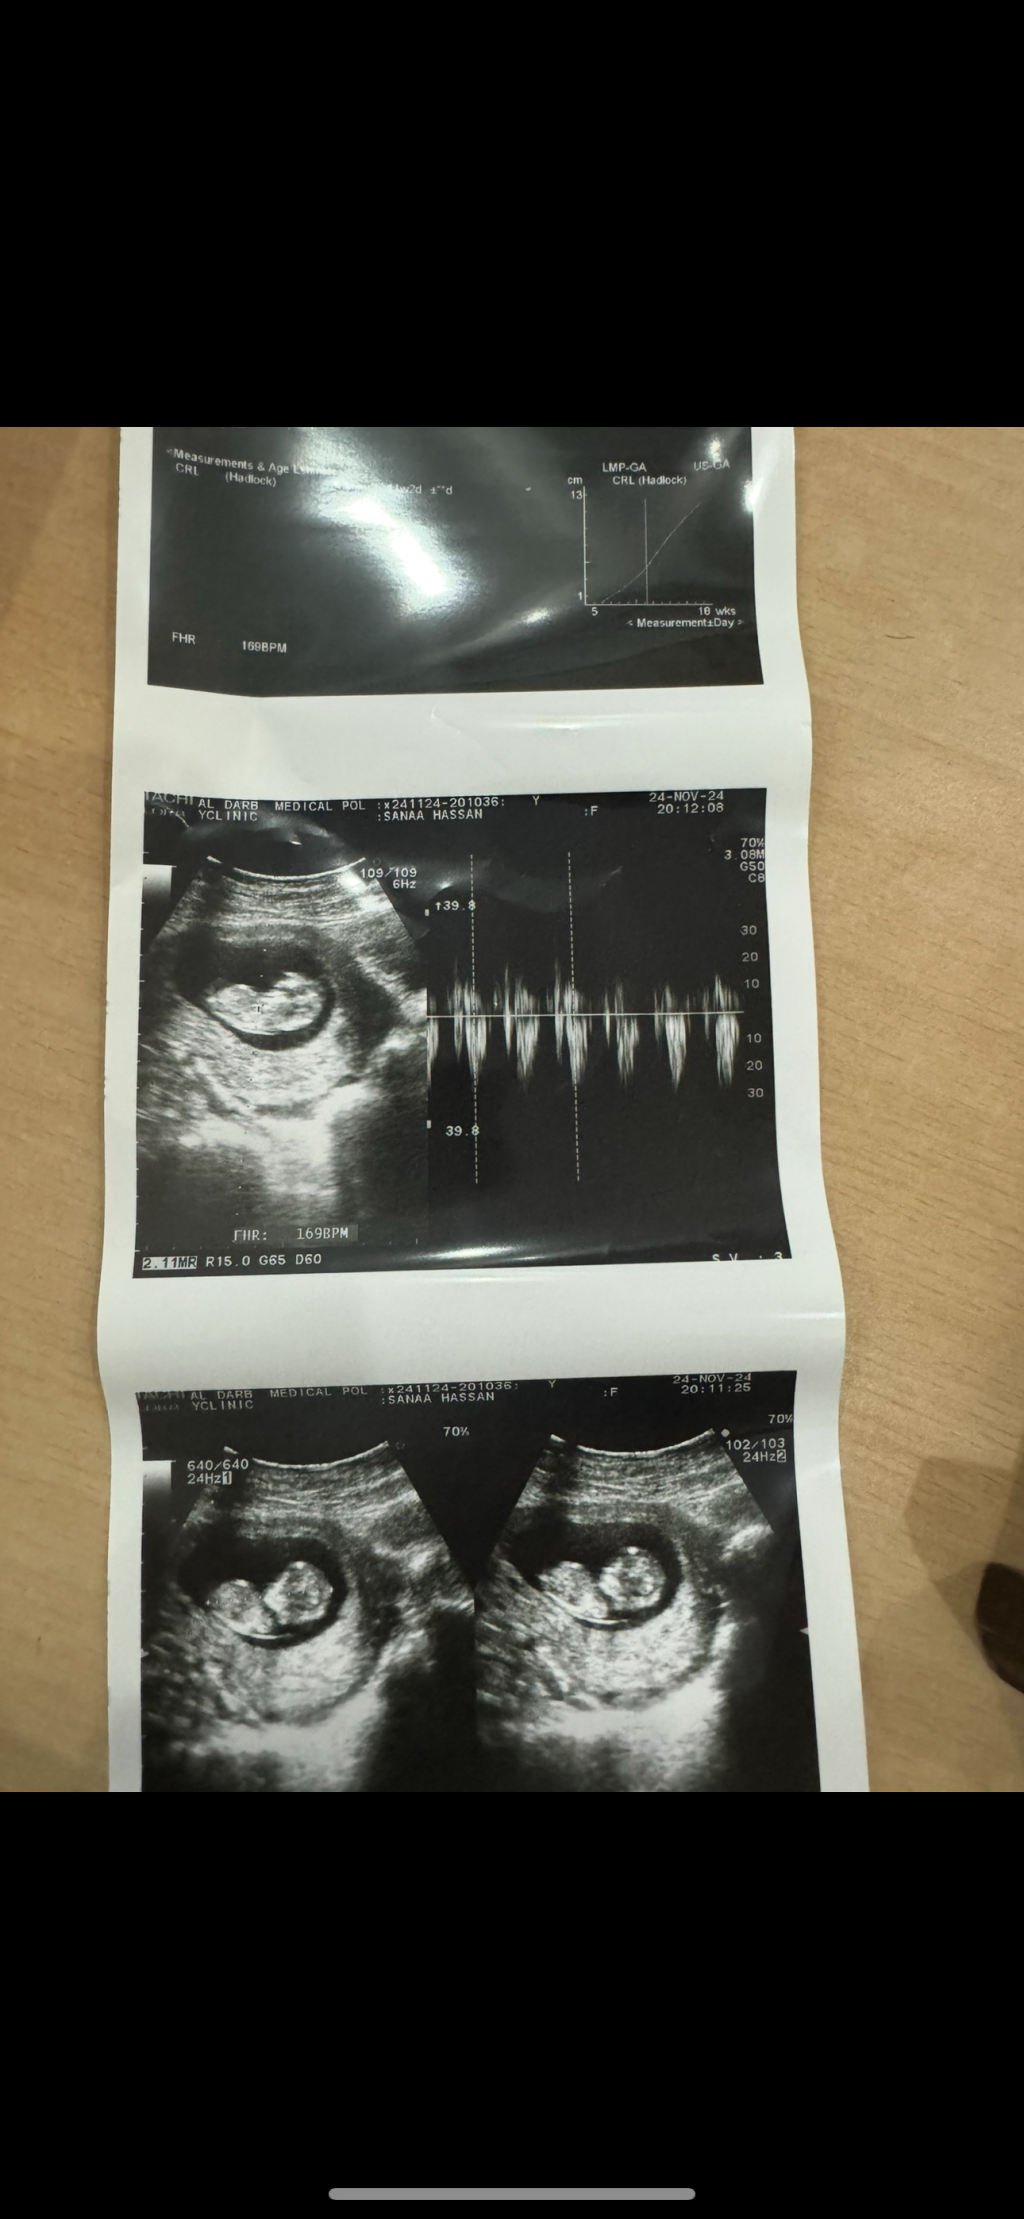

سونار الي تعرف

اسبوع ١١